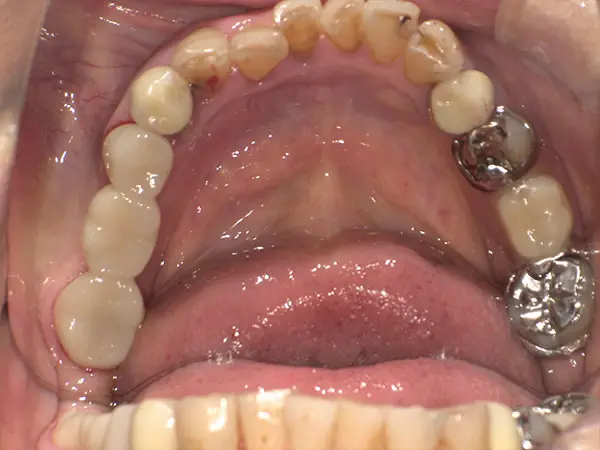

上顎前突

術前正面

術前上顎

術前下顎

術後正面

術後上顎

術後下顎

術中上顎

術中下顎

| 主訴 | 出っ歯 |

| 初診年齢 | 37歳 |

| 治療内容・装置 | 自費、表側マルチブラケット、アンカースクリュー |

| 抜歯・非抜歯 | 抜歯 |

| 治療期間 | 2年 |

| 費用 | 1,038,400円(税込) (相談料、検査料、診断料、動的治療費、保定期間料、抜歯代、アンカースクリュー費等含む) |

| 治療のリスク・副作用 | 歯の移動に伴う痛み 上下顎前歯部の歯根吸収 装置による口内炎 ブラッシング不良によるむし歯・歯肉炎 |